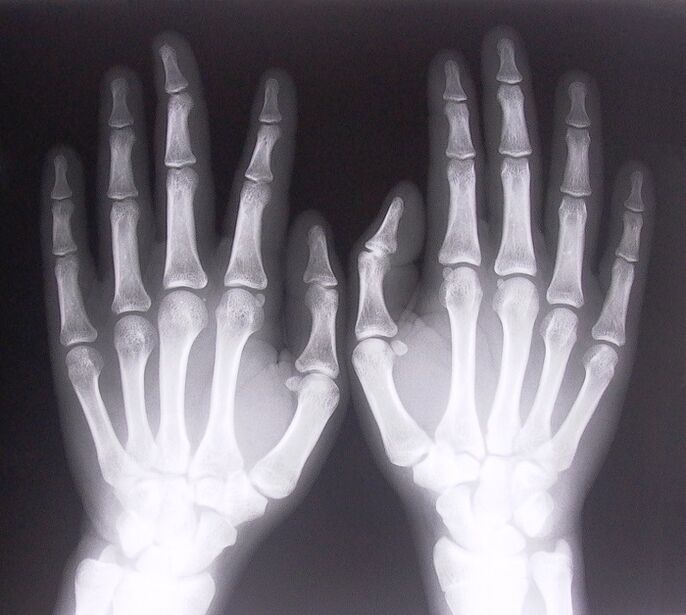

- Stenozan ligamanit. Hastalığın nedenini belirlemek için röntgen çekmek gerekir. Semptomlar tipiktir: elin ağrılı hareketi, sıkılmış avuç içi kıvrımı. Ayrıca uzatma sırasında genellikle tıklamalar duyulur.

- Röntgen çekin.